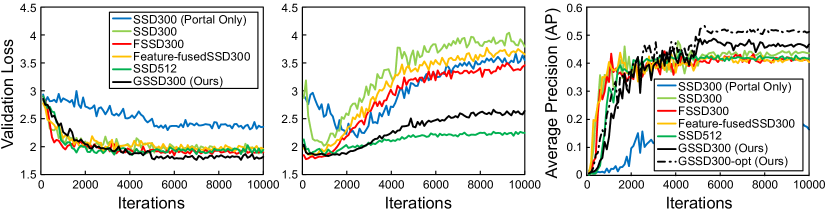

The performance definitively improved when using the multi-phase data. For comparison, the single-phase model received portal phase images copied four times as inputs. The model trained with only the portal phase data obviously underfitted (Figure 3), since several variants of the ground truth lesions are barely visible from the portal CT images.

By significantly suppressing overfitting of the class confidence layers (Figure 3), our grouped SSD (GSSD) outperformed the original model as well as recently proposed state-of-the-art variants (Table 1) [18, 19]. Figure 4 demonstrates qualitative detection results. The best configuration achieved a 53.3% average precision (AP) score (Table 1). The model runs approximately 40 slices per second and can go through an entire volume of 100 slices in under three seconds on an NVIDIA Tesla P100 GPU. Note that the 1x1 convolutions play a key role as channel selectors. GSSD failed to perform well without the module. Stacking the 1x1 convolutions on top of the original model did not improve its performance, which proved that the combination of grouped convolutions and the channel selector module best harnesses the multi-phase data distribution.